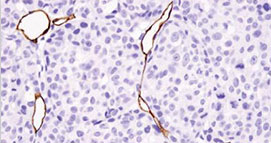

7、免疫組化染色

應(yīng)用免疫學(xué)基本原理——抗原抗體反應(yīng)����,即抗原與抗體特異性結(jié)合的原理,通過化學(xué)反應(yīng)使標(biāo)記抗體的顯色劑(熒光素�����、酶����、金屬離子、同位素)顯色來確定組織細(xì)胞內(nèi)

抗原(多肽和蛋白質(zhì))�����,對(duì)其進(jìn)行定位���、定性及相對(duì)定量的研究���。